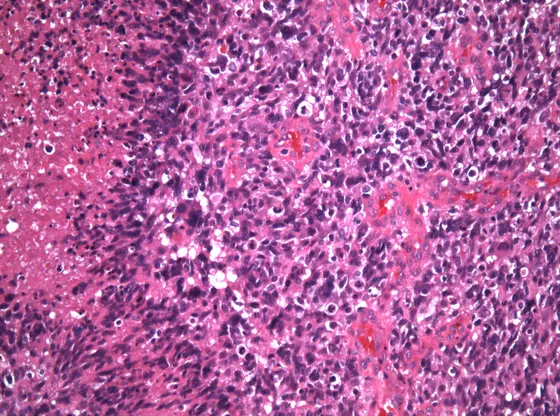

Für diesen Nachweis übertrugen die Forscher MET-Fusionsgene auf Mäuse, die daraufhin genau diese Art von Hirntumoren – Glioblastome – entwickelten. An diesen Tieren konnten die Forscher anschließend bestätigen, dass die MET-Inhibitoren das Krebswachstum deutlich verlangsamten.